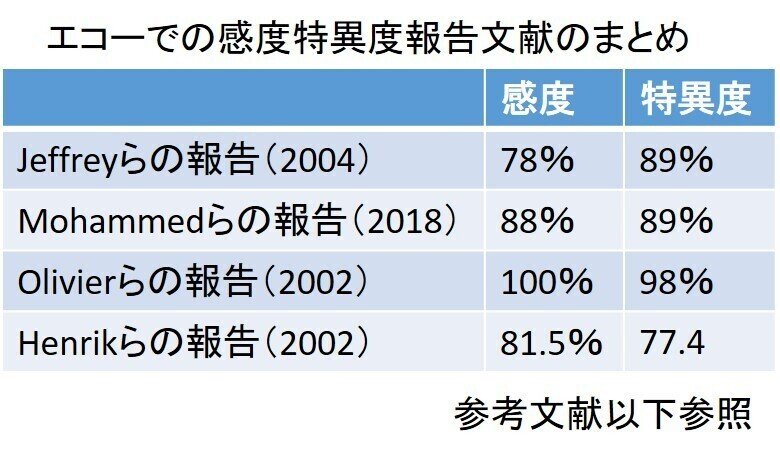

舟状骨骨折って,エコーどうなん?

さぁ結論から行きます

めっちゃ使えます👇参照

さらに Olivierらの報告によれば

超音波観察時の骨皮膜の破壊が診断の鍵となる。

軟部組織の異常だけでは特異性に欠けると

言われている